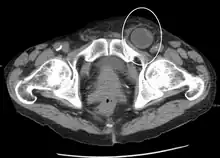

An inguinal hernia which contains part of the bladder. Bladder cancer also present.

When assessed by ultrasound or cross sectional imaging with CT or MRI, the major differential in diagnosing indirect inguinal hernias is differentiation from spermatic cord lipomas, as both can contain only fat and extend along the inguinal canal into the scrotum.[22]

On axial CT, lipomas originate inferior or lateral to the cord, and are located inside the cremaster muscle, while inguinal hernias lie anteromedial to the cord and are not intramuscular. Large lipomas may appear nearly indistinguishable as the fat engulfs anatomic boundaries, but they do not change position with coughing or straining.[22]